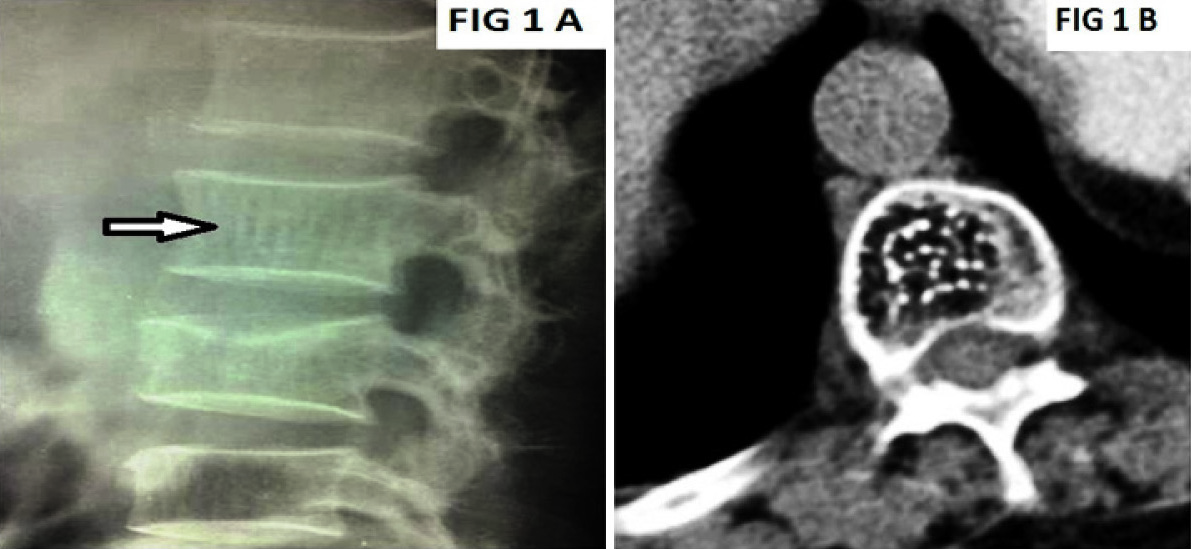

Conventional lateral radiograph of the lumbar spine [Table/Fig-1a] shows the classic corduroy cloth appearance (vertical striations) {white open arrow}, Axial CT of the lumbar spine [Table/Fig-1b] depicts polka dot appearance. Sagittal images of MRI spine T1WI [Table/Fig-2a], T2WI [Table/Fig-2b] and fat suppressed STIR images [Table/Fig-2c] show well defined oval lesions (white open arrow) involving lower thoracic and lumbar vertebrae appearing Hyperintense on T1WI and T2WI images and Hypointense on STIR images.

Vertebral hemangiomas (a) lateral view, (b) axial view

The thickened vertical trabeculae of hemangiomas cause parallel linear densities or a “jail bar” appearance (white open arrow) in the vertebral body on plain films. On axial computed tomography (CT), the remaining thickened trabeculae give a typical spotted appearance to the vertebral bodies [1]. MR is extremely sensitive in the detection of hemangiomas. On both T1-weighted and T2-weighted images, these lesions tend to have increased signal intensity [2]. Occasional hemangiomas within the bony confines can have a somewhat lower amount of adipose tissue and even appear diffusely hypointense [3]. MR is able to show paravertebral and epidural extension of tumour [1].